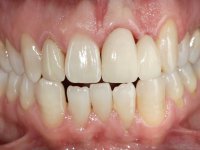

Fifty year old male patient, non-smoker. Carries a Maryland Bridge replacing tooth 2.2. "Maryland wings" are metallic and the dental surfaces in contact with them are infiltrated. Tooth 2.1 had a feldspathic ceramic veneer covering the vestibular surface. Tooth 1.2 presented a feldspathic ceramic veneer with exposed cervical margin. The edentulous space corresponding to tooth 2.2 is narrow and tall. Patient presents an open anterior bite, good oral hygiene and reasonable periodontal health.